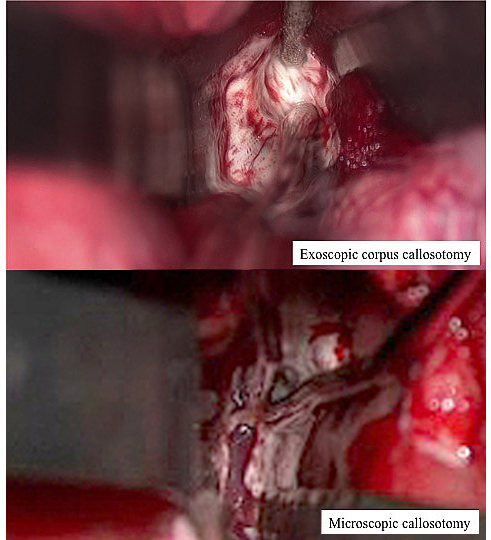

The visual quality of magnified images on the 4K-3D monitor produced by the exoscope was uniformly perceived by all surgeons and medical staff. Stereoscopic vision was easily obtained. Moreover, we felt that the exoscope provided higher-quality magnification, compared to the operating microscope (Fig. 3). Luminosity of the exoscope light was high, providing a bright, broad surgical field. For epilepsy surgery that deals with normal-appearing white matter fibers, rather than brain tumors or vascular abnormalities, being able to adjust the luminosity intraoperatively is particularly important because white matter is easily blurred by halation effects. If the exoscope light was too bright, and the corpus callosum was blurred due to halation effects, we decreased the illumination. Under lower light conditions, we were able to confirm the anatomy without difficulty.

Fig. 3.

Fig. 3.View of the surgical field. Exoscopic corpus callosotomy shows a wider view than microscopic callosotomy.